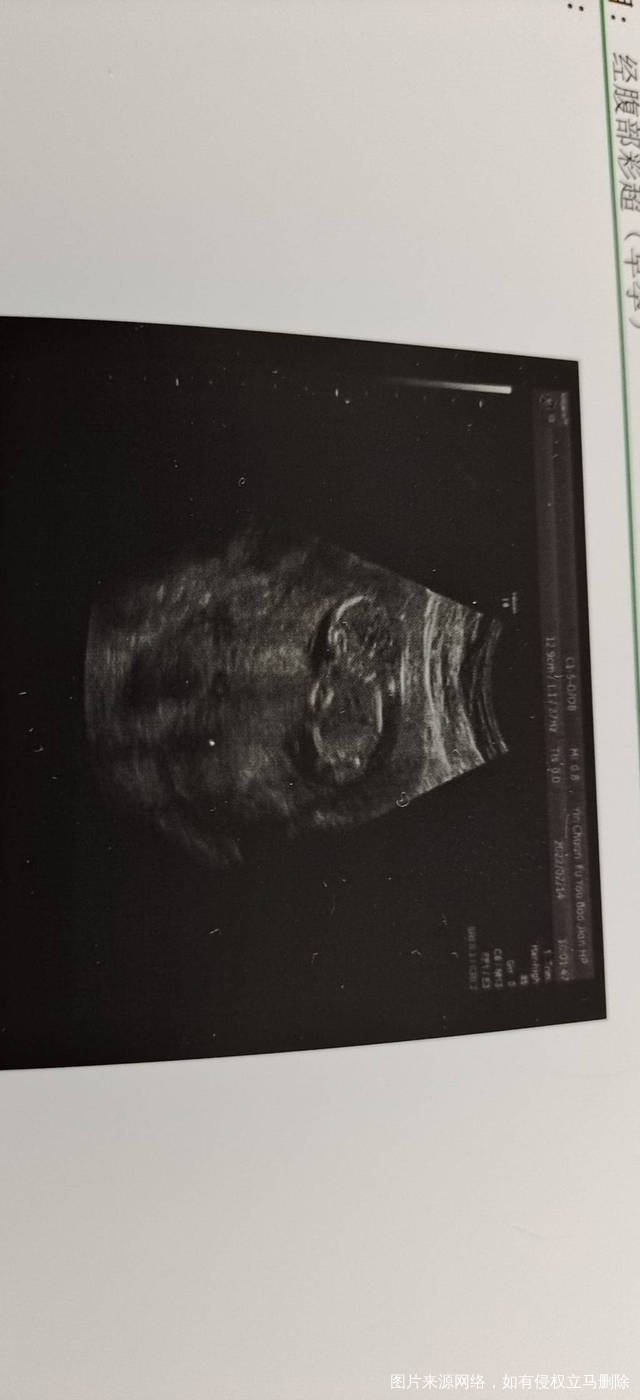

今天是怀孕16周去做了胎心监测还有做了一个B

正常的胎盘附着于子宫体部的前壁、后壁或侧壁,远离宫颈内口。妊娠28周后,胎盘仍附着于子宫下段,其下缘达到或覆盖宫颈内口,位置低于胎儿先露部,称为前置胎盘。你的情况,现在孕周还小,还不能确定是前置胎盘。遵医嘱用药吧!注意休息,观察是否有阴道流血,如果有阴道流血,及时去医院。